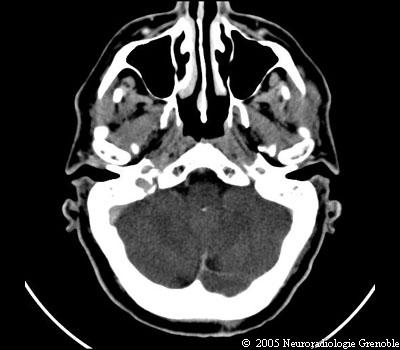

Radioanatomie TDM de l'encéphale

TDM cérébrale sans injection